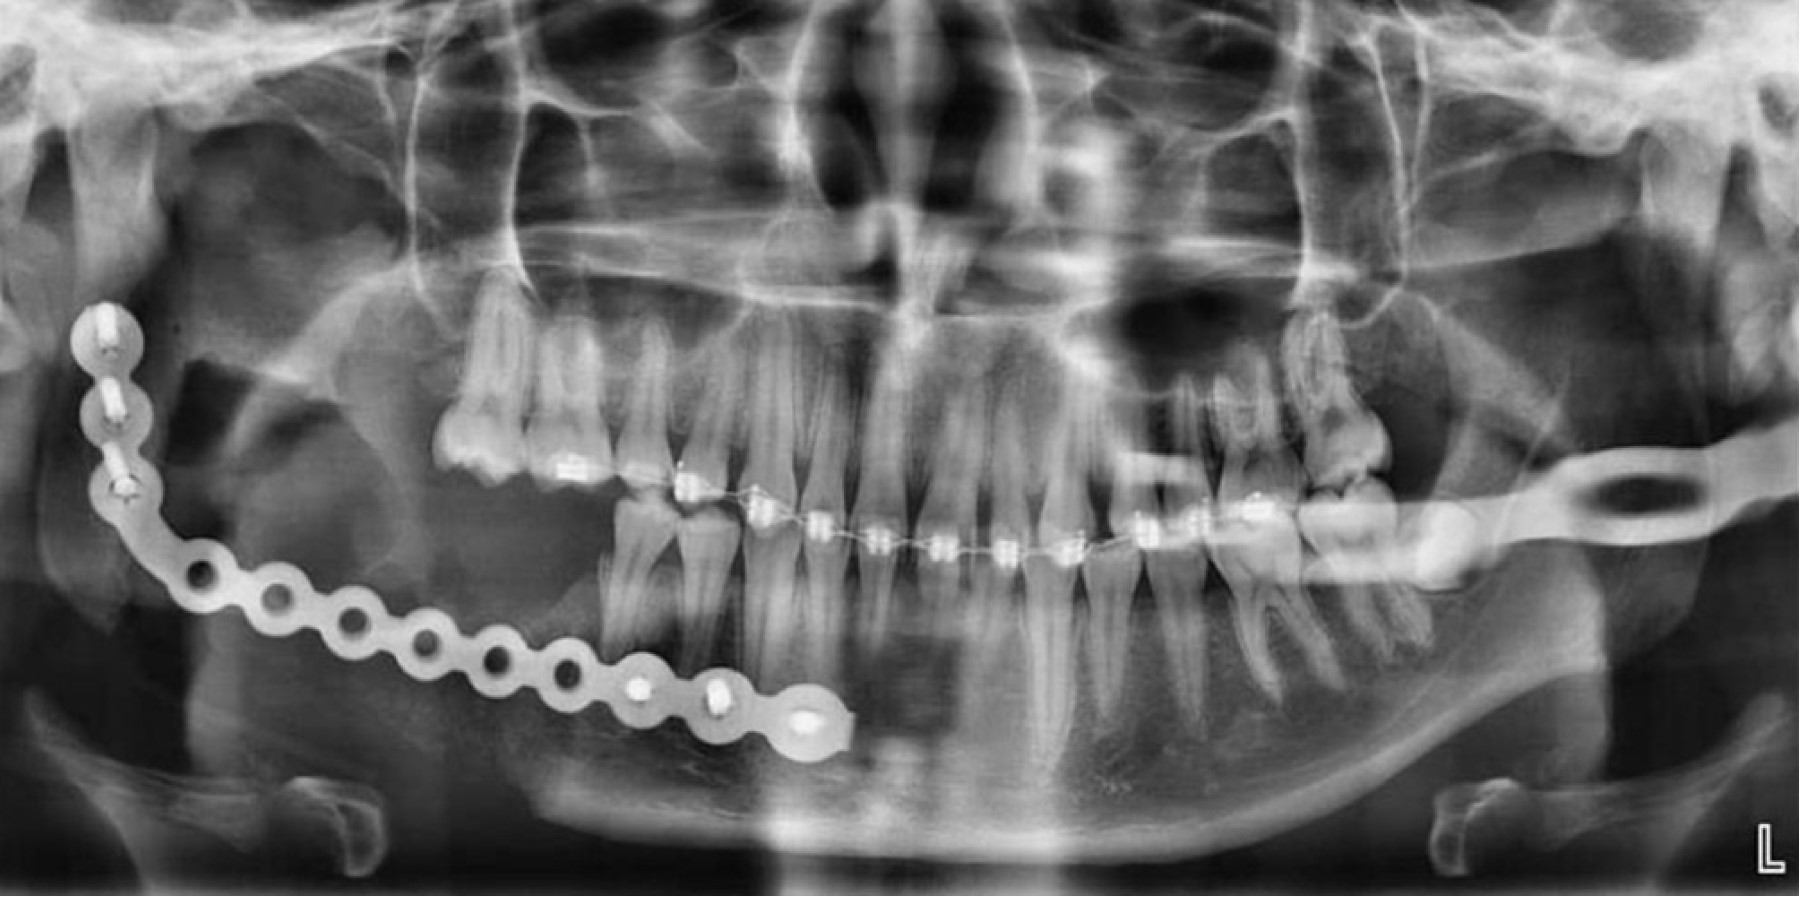

La razón fundamental para el desarrollo y el uso de la planificación quirúrgica virtual (PQV) es optimizar la capacidad del cirujano para prepararse y mitigar posibles contratiempos en el quirófano. En la literatura se encuentra relativamente poca evidencia sobre la aplicación de la PQV en procedimientos quirúrgicos complejos, aún más escasa en la literatura se refleja la bondad que ofrece la PQV en cuanto a la elección del abordaje quirúrgico. Este estudio presenta el abordaje de una lesión benigna mandibular extensa y su reconstrucción con material de osteosíntesis. Todo ello asistido por un software virtual de planificación quirúrgica que permitió realizar la ejecución virtual de la cirugía, la planificación del abordaje más conveniente para la extirpación de la lesión mediante guías quirúrgicas y la posterior reconstrucción. Enfatizando el análisis de los beneficios de la PQV y su influencia en la elección del abordaje quirúrgico más ideal y menos invasivo para el caso.

Figura 2